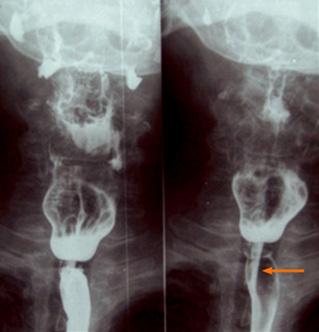

Figura 10. A. Anatomía normal con triangulo de Killian B. diverticulo de Zenker de Plummer Vinson (síndrome de Patterson Kelly) años)

Figura 11. Esofagograma. Presencia de membrana a nivel del esófago cervical que solo permite un paso filiforme de contraste (flecha)

Figura 12. Una delgada membrana semilunar se proyecta hacia la luz en la parte superior del esófago, junto con la anemia por deficiencia de hierro (coiloniquia) y la disfagia forman parte de la tríada clásica del síndrome de Plummer-Vinson. Figura 13. Trastornos motores del esófago. A: Acalasia; B: Espasmo difuso del esófago; C: Esclerodermia Figura 14 Cáncer de esófago produce disfagia mecánica progresiva con baja de peso significativo